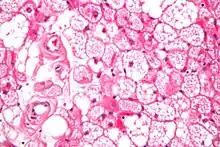

Hibernoma (intermediate magnification).

The tumors histologically resemble brown fat. There are four histologic types recognized, but one is the most frequently seen (typical). There is a background of rich vascularity.

- Lobular type: Variable degrees of differentiation of uniform, round to oval cells with granular eosinophilic cells with prominent borders, alternating with coarsely multivacuolated fat cells (pale cells). There are usually small centrally placed nuclei without pleomorphism. The cells have large cytoplasmic lipid droplets interspersed throughout.[3][4]

- Myxoid variant: Loose, basophilic matrix, with thick fibrous septa, and foamy histiocytes

- Lipoma-like variant: Univacuolated lipocytes, with only isolated hibernoma cells

- Spindle cell variant: Spindle cell lipoma combined with hibernoma